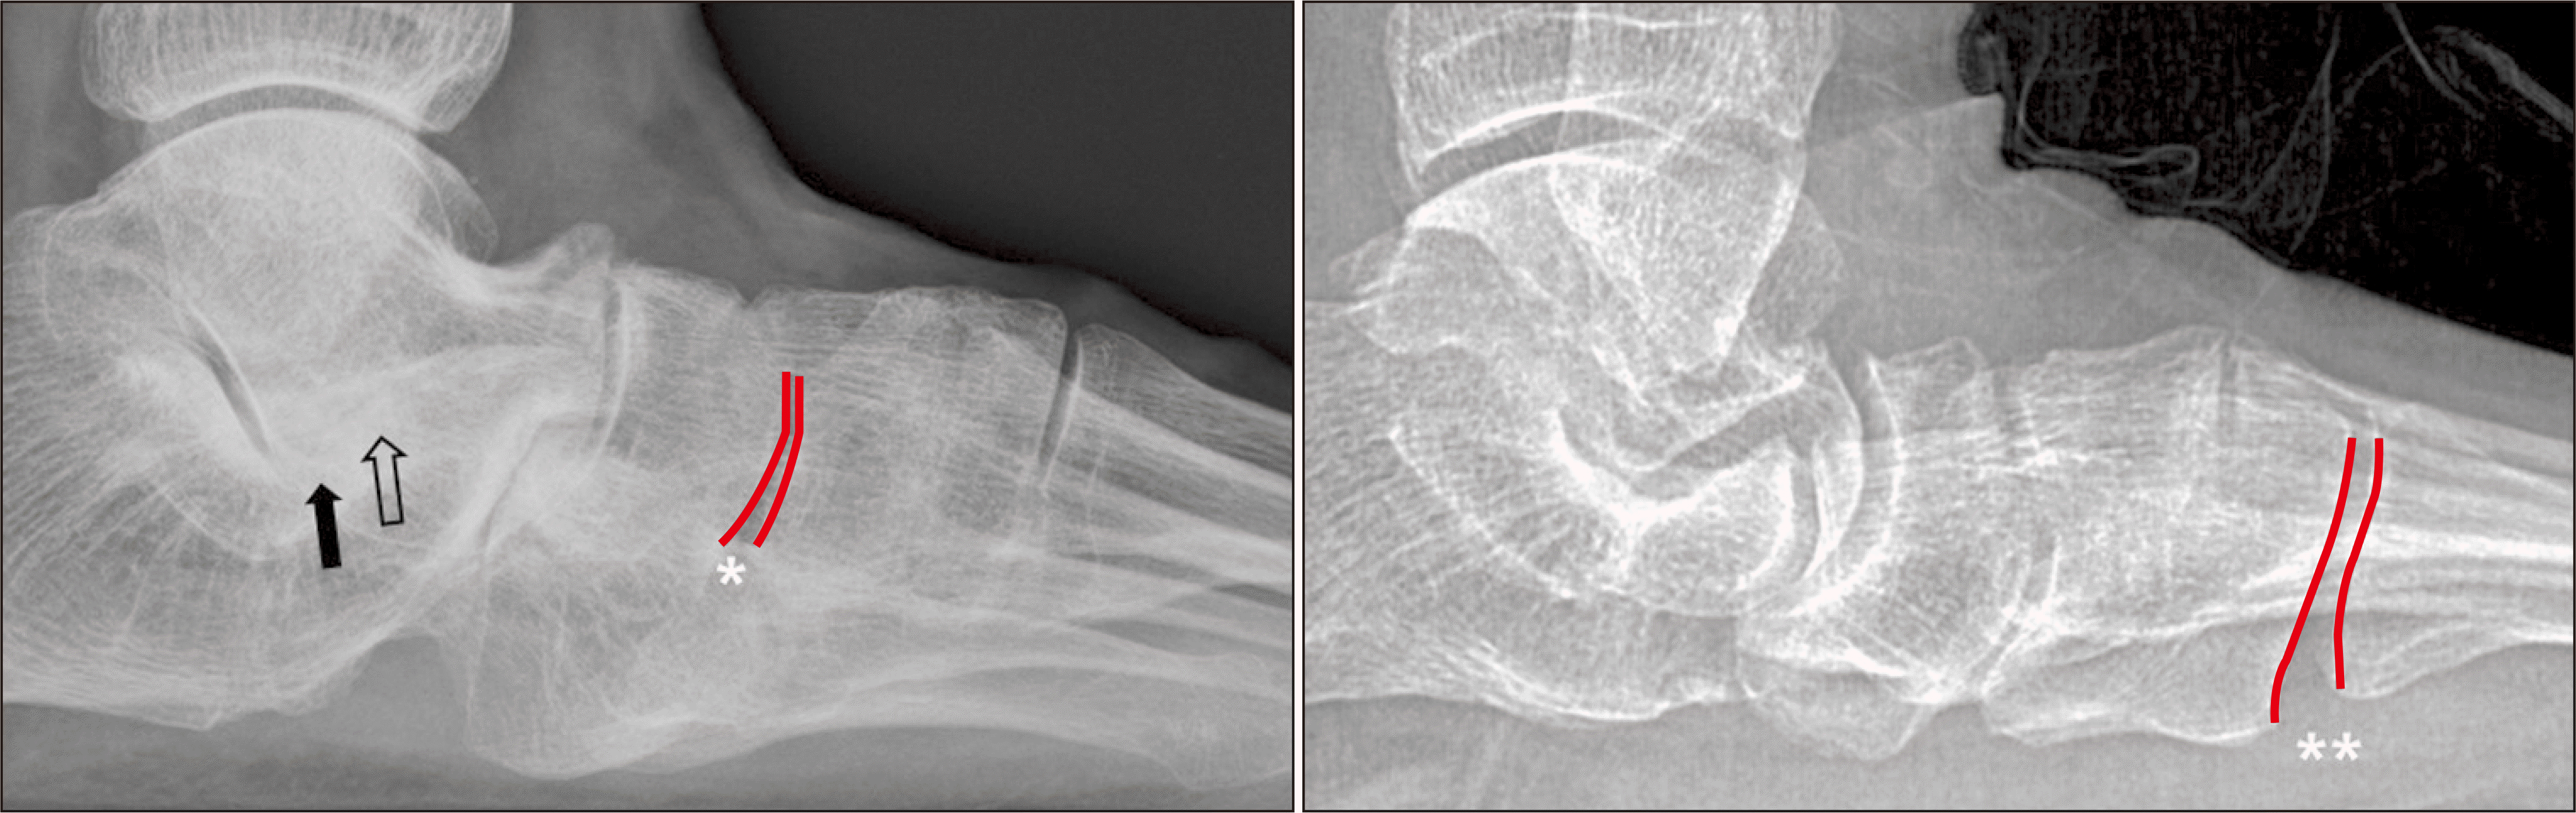

체중부하 방사선 촬영은 편평족의 진단에 있어 가장 표준이 되는 검사로, 체중부하 족부 전후면, 족부 측면, 족관절의 전후면 혹은 모티스 영상(mortise view) 및 후족부 정렬 촬영(hindfoot alignment view)8) 등이 진단을 위해 권고된다.9) 족부 전후면 사진에서는 전족부 혹은 중족부의 외전 정도를 평가할 수 있으며 거주상 관절 피복각(talonavicular coverage angle), 거주상 관절 이탈률(talonavicular uncoverage percent) 등 이를 반영하는 매우 다양한 지표를 측정할 수 있다(Fig. 1). 족부 측면 사진에서는 내측 세로궁의 소실 정도를 평가할 수 있는데, 흔히 쓰이는 지표로는 Meary angle이라 불리는 외측 거골-제 1중족골 각도를 측정할 수 있다(Fig. 2). 또한 족부의 내측주(medial column) 관절들의 족저부 벌어짐(plantar gapping) 정도를 확인하여 내측주 불안정성 정도를 평가할 수 있으며 족근동에서 거골과 종골의 직접적인 충돌 혹은 족근동 주변 골의 경화소견이나 낭종성 병변 등을 통해 족근동 충돌을 간접적으로 확인할 수 있다(Fig. 3). 족관절의 전후방 혹은 모티스 사진에서는 거골의 외반경사(valgus talar tilt)의 유무를 통해 족관절의 불안정성을 평가할 수 있으며 변형이 많이 진행한 경우 비골하 충돌 또한 확인할 수 있다(Fig. 4). 마지막으로, 후족부 정렬 촬영을 통해서는 후족부 외반 변형의 정도를 평가할 수 있는데, 주로 후족부 정렬각(hindfoot alignment angle) 혹은 후족부 모멘트암(hindfoot moment arm)을 측정한다(Fig. 5).10)

새로운 분류체계는 변형의 종류와 위치에 따라 A~E로 나누고, 각 변형의 유연성 유무에 따라 1기 유연성 변형과 2기 강직성 변형으로 분류하였다(Table 2).6) 이러한 변형은 진찰 소견과 체중부하 단순 방사선 촬영을 통해 평가하도록 하였고, 체중부하 전산화 단층촬영의 경우 아직 전세계적으로 사용되고 있지는 않기 때문에 판단기준에서 제외되었다. A형 변형은 후족부 외반 변형으로 후족부가 신체의 정중선으로부터 외측으로 전위된 변형을 뜻한다. 임상적으로 진찰 시 후족부 외반이 관찰되거나, 후족부 정렬 영상에서 후족부 정렬각 혹은 후족부 모멘트암의 증가 등으로 판단할 수 있다(Fig. 5). B형 변형은 전족부 혹은 중족부의 외전 변형으로 전족부나 중족부가 후족부를 기준으로 외측으로 전위된 변형이다. 체중부하 족부 전후면 사진상 거골두에 대한 주상골의 피복(coverage) 정도가 감소하고, 거주상 관절 피복각이 증가한다(Fig. 1). 또한 이 변형에 의해 족근동 충돌이 발생할 수 있으며, 족근동 주변의 압통 및 통증이 발생할 수 있다. 체중부하 족부 측면사진상 족근동에서 거골과 종골의 직접적인 충돌 소견이 보이거나, 족근동 주변의 거골과 종골의 골경화 혹은 골낭종 등을 통해 간접적으로 확인할 수 있다(Fig. 3). C형 변형은 전족부의 내반 변형 혹은 내측주 불안정성으로 임상적으로 후족부를 중립 위치에 고정한 뒤 관찰하였을 때 전족부가 내반을 보이는 변형이다(Fig. 8). 일부에서는 이를 회외 변형으로 불러야 한다는 의견도 있으나 현재 혼용해서 쓰이고 있다.11,20) 내측주 불안정성은 체중부하 족부 측면사진상 거주상 관절, 주상설상 관절(naviculocuneiform joint) 및 족근중족 관절(tarsometatarsal joint)이 배측 불안정증을 보이는 것으로, 영상검사상 족저부 벌어짐 유무 등을 통해 내측주 불안정성의 유무 및 위치를 확인할 수 있다(Fig. 3). D형 변형은 거근관절의 탈구 혹은 아탈구 변형으로 거골이 종골을 기준으로 내회전, 족저굴곡되면서 종골은 거골을 기준으로 외회전, 외반, 외측 전위가 발생하면서 거골하 관절의 아탈구가 발생하고, 심한 경우 비골하 충돌을 일으키게 된다(Fig. 4). E형 변형은 발목관절의 외반 변형이 발생한 경우이며, 족관절의 전후방 혹은 모티스 사진에서 거골의 외반경사로 확인할 수 있다(Fig. 4). 이 분류의 적용은 한 환자에 대해 A 부터 E까지의 변형 유무를 확인하고, 각각의 변형이 유연성 변형인지, 강직성 변형인지에 따라 1기와 2기를 나누는 방식으로 적용한다.

Figure 3

Weight bearing foot lateral radiograph showing plantar gapping of naviculocuneiform joint (*) and tarsometatarsal joint (**). Sinus tarsi impingement (black arrow) and bony sclerosis around sinus tarsi (white arrow).